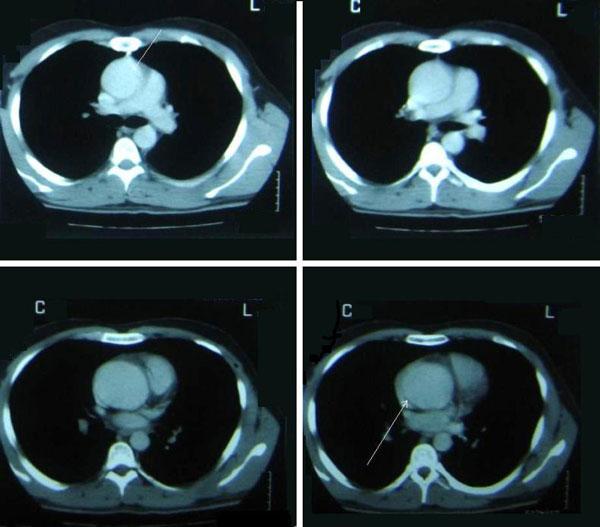

The patient is a 26-year-old Caucasian Greek male who was presented in the emergency department with acute chest pain. Computerized tomography with contrast material showed the presence of an ascending aortic aneurysm with the question of an acute dissection type A (De Bakey II). The patient was emergently operated with replacement of the affected aortic segment and he had an uneventful clinical course. Three years follow up is essentially normal.

该患者是一名26岁的白种希腊男性,因急性胸痛被送至急诊科。增强计算机断层扫描显示升主动脉瘤,怀疑为A型急性夹层(De Bakey II型)。患者紧急接受手术,置换了受影响的主动脉段,临床过程顺利。三年随访基本正常。